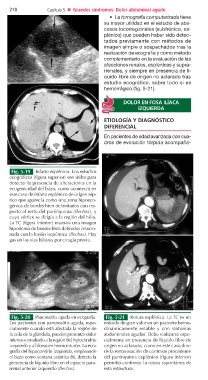

Fig. 5-19 Infarto esplénico. Los estudios

ecográficos (figura superior) son útiles para

detectar la presencia de alteraciones en la

ecogenicidad del bazo, como aconteció en

este caso de infarto esplénico de origen sép-

tico que aparecía como una zona hipoeco-

génica de bordes bien delimitados con res-

pecto al resto del parénquima (flechas), y

cuyo vértice se dirigía a la región del hilio.

La TC (figura inferior) muestra una imagen

hipodensa de bordes bien definidos relacio-

nada con la lesión isquémica (flechas). Hay

gas en las vías biliares por cirugía previa.

Fig. 5-20 Pancreatitis aguda en ecografía. Fig. 5-21 Rotura esplénica. La TC es un

Los pacientes con pancreatitis aguda, espe- método de gran valor en un paciente hemo-

cialmente cuando está afectada la región de dinámicamente estable y con síntomas

la cola de la glándula, pueden presentar dolor abdominales agudos. Debe realizarse espe-

intenso e irradiado a la región del hipocondrio cialmente en presencia de líquido libre de

izquierdo y al dorso en hemicinturón. La eco- origen no aclarado, como en este caso don-

grafía del hipocondrio izquierdo, empleando de la extravasación de contraste procedente

el bazo como ventana acústica (b), detecta la del parénquima esplénico (figura inferior)

presencia de líquido libre en el espacio para- permitió confirmar la rotura espontánea de

rrenal anterior izquierdo (flechas). esta estructura.